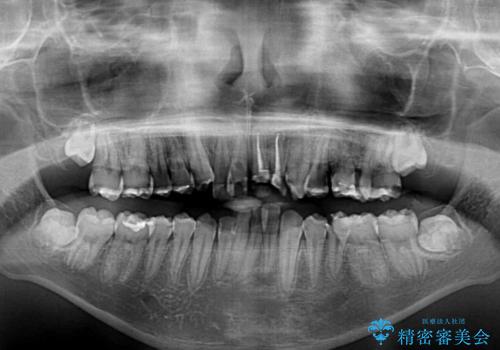

前歯のデコボコとむし歯だらけの歯列 矯正治療と虫歯治療

- むし歯が多く、歯並びも悪いとのことで、以前通院されていたご家族の紹介で来院された患者様です。

口腔内に無頓着であったため、まずはしっかりと歯磨きトレーニングを行い、必要な虫歯治療を行いました。

矯正治療は、むし歯が酷く抜歯が望ましい歯を1本抜歯して、ワイヤー装置にて整えることとしました。

矯正治療後は上顎前歯4本をオールセラミッククラウンにて補綴治療を行うこととしました。